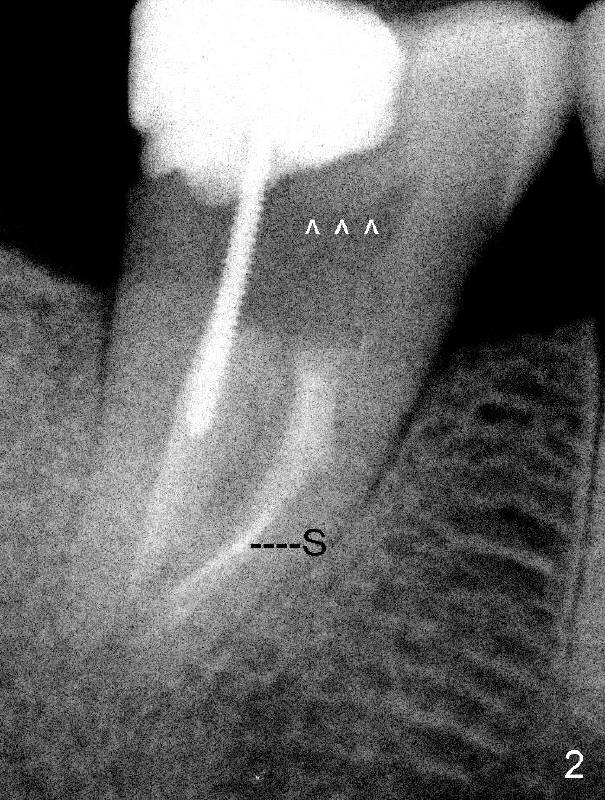

A 50-year-old lady presents to clinic with chief complaint "I need a new filling in the lower right". Root canal has been done in her home country without symptoms for several years. Exam reveals that the tooth #31 has DO composite. The mesial portion of the restoration has chipped (Fig.1: black arrowhead). There is 2nd caries in the distal margin (white arrowhead). Percussion reveals minimal tenderness. Crown is recommended. In addition to the post (P) and core (C), what is special about this case?

In fact, there is a separated file in the mesial canal (Fig.2: S). The related problem is that the mesial portion of the pulpal roof is not removed (arrowheads). The access to the pulp is limited (Fig.3: red lines), particularly to the mesial canal. The file must have been bent twice (pink line in an S shape) before separation. By comparison, the access to the pulp of another lower 2nd molar is sufficient (Fig.4 red lines) and the file is bent only once (pink line).